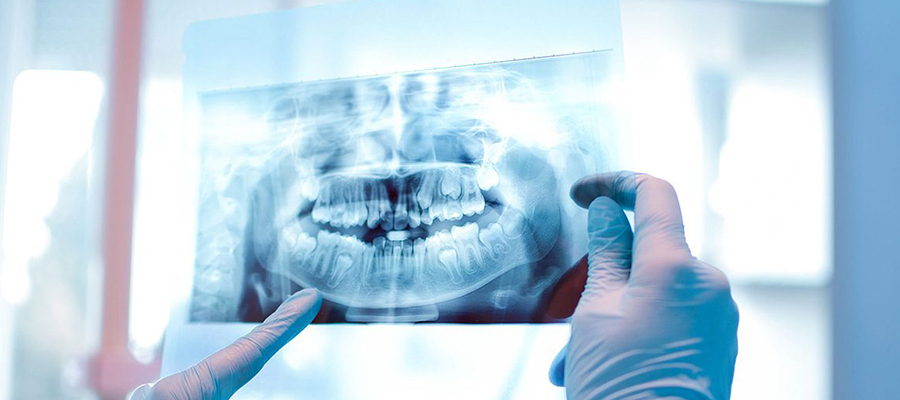

Панорамный рентген, также известный как панорамная рентгенография или ортопантомография (OPG), – это специализированный метод визуализации, используемый для получения единого панорамного изображения всей полости рта, включая зубы, челюсти и окружающие структуры. Этот передовой метод визуализации предоставляет ценную информацию для диагностики различных заболеваний зубов и полости рта и является важным инструментом в стоматологии и челюстно-лицевой хирургии. В Aktif International Hospitals мы предлагаем комплексные услуги панорамного рентгена, выполняемые опытными рентгенологами с использованием самого современного оборудования для обеспечения точных и подробных результатов визуализации.

Панорамный рентген – это специализированный стоматологический рентген, который позволяет получить панорамный вид всей полости рта, включая зубы, челюсти, височно-нижнечелюстные суставы (ВНЧС) и окружающие структуры. Этот метод визуализации предоставляет ценную информацию для диагностики широкого спектра заболеваний зубов и полости рта, включая кариес, заболевания десен, аномалии челюсти, удаленные зубы, инфекции полости рта и опухоли полости рта. Панорамные рентгеновские снимки обычно используются при обычном стоматологическом осмотре, планировании лечения при ортодонтических и хирургических операциях в полости рта, а также для оценки состояния полости рта в целом.

Во время процедуры панорамного рентгена пациент стоит или сидит в вертикальном положении, а рентгеновский аппарат вращается вокруг головы полукругом. Пациент прикусывает зубами или опирается подбородком на подставку для подбородка, чтобы обеспечить правильное расположение и выравнивание. Рентгеновский аппарат испускает сфокусированный пучок рентгеновских лучей, которые проходят через структуры полости рта и фиксируются цифровым датчиком или пленкой на противоположной стороне. Весь процесс занимает всего несколько секунд, а полученный панорамный снимок дает полное представление о всей полости рта в одном изображении.